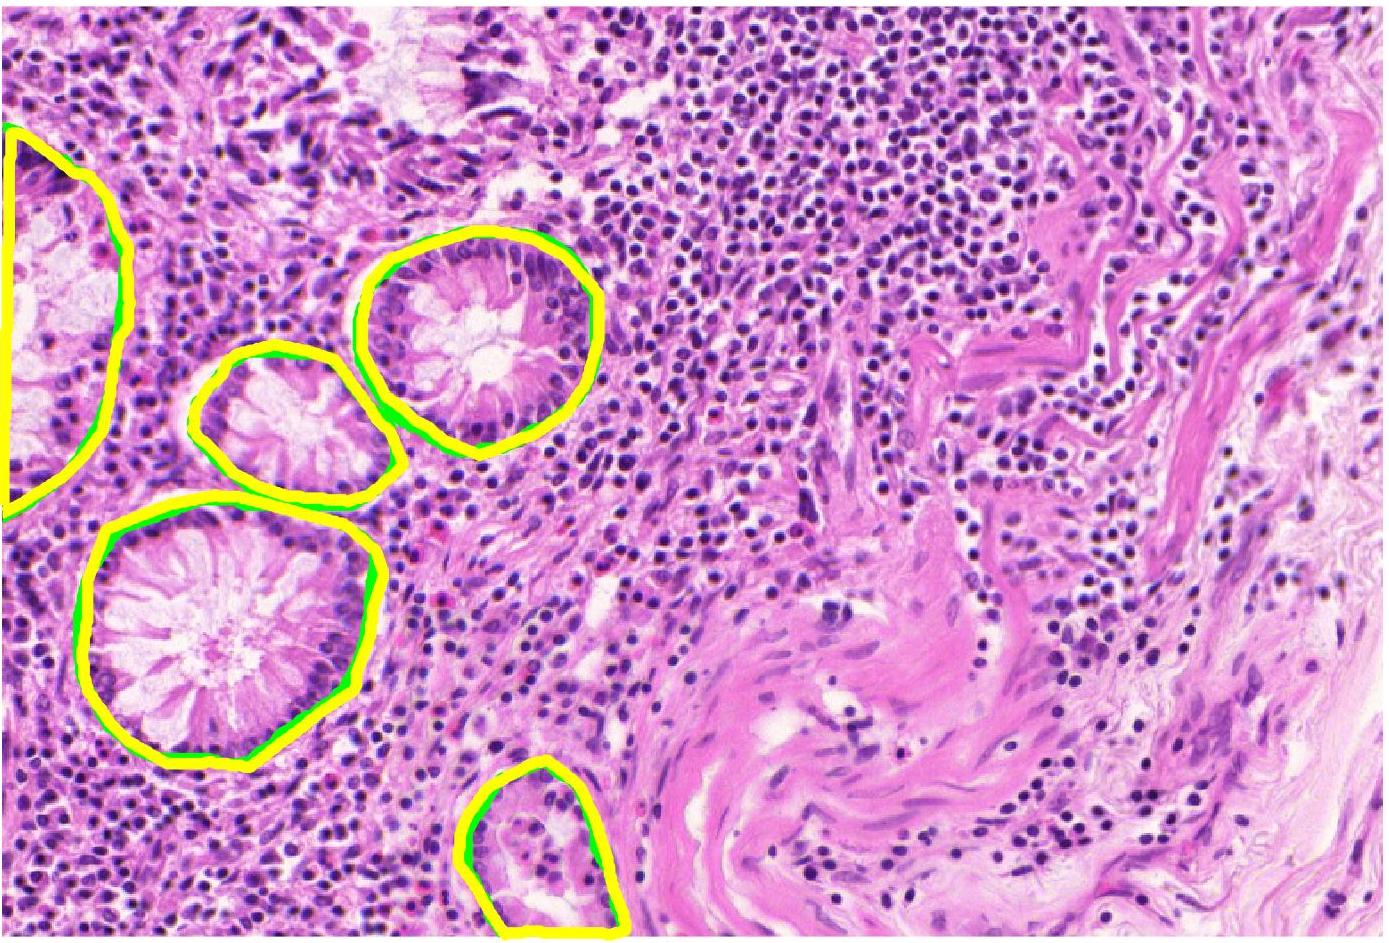

Ground truth maps obtained from the semi-supervised learning step has labels for each block. Consequently, there will be cases where a pixel outside the actual structure of interest shares its label since it is part of the block. This erroneous labeling is referred as label noise. Our experimental results show that the UNet++ network is more robust to such label noise than the conventional UNet. Figure 4 shows comparative results of using UNet and UNet++ in obtaining the weak segmentation map. UNet++ proves to be more robust to initial label noise. Figure 5 shows example images, their corresponding expert annotated manual segmentation maps, and the maps obtained using our method. A very high degree of agreement exists between weak supervision generated maps and the ground truth, with a Dice Metric of validating this observation. Without the label refinement step we obtain a Dice Metric of , highlighting its contribution in improving segmentation performance. Using UNet we obtain a Dice metric of and (without label refinement), which indicates superior capacity of UNet++ to overcome label noise. Thus we repose high confidence in the weakly supervised generated label maps as representing the correct labels and are reliable enough to model inter-label geometric relationship (as described in the next step).

We apply our method on the public GLAS segmentation challenge [189], which has manual segmentation maps of glands in stained images derived from histological sections from different patients with stage or colorectal adenocarcinoma. The slides were digitized with a Zeiss MIRAX MIDI Slide Scanner having pixel resolution of m. The WSIs were rescaled to a pixel resolution of m (equivalent to magnification). visual fields from malignant and benign areas from the WSIs were selected to cover a wide variety of tissues. An expert pathologist graded each visual field as either ‘benign’ or ‘malignant’. Further details of the dataset can be found at [189].

We generate augmented images using GeoGANWSS and train a UNet++ segmentation network to obtain the final output. The performance metrics - Dice Metric (DM), Hausdorff distance (HD), F1 score (F1)- for our results (including ablation studies) and top-ranked methods [190, 189] are summarized in Table V. The numbers are taken from the challenge paper in [189] (Table 2). Except for GeoGANManual (equivalent to fully supervised training), our method, GeoGANWSS, outperforms all other methods using a standard segmentation architecture. The ablation study experiments’ performance also demonstrates the benefits of including all components of our proposed method. Competing methods in the challenge have used conventional augmentation, whereas our image synthesis approach generates more informative images.

Figure 8 shows example segmentation outputs of GeoGANWSS and other variants of our method used for ablation studies. The results clearly show that with the exclusion of our proposed method’s different components, the segmentation performance degrades.